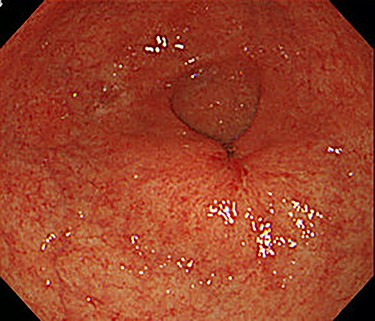

Chest and abdominal computed tomography (CT) showed no distant metastasis, but the tumor of the antrum was clearly visualized and was located close to the pancreatic head (Fig. 1). EGD revealed a large ulcerated lesion at the greater curvature of the antrum (Fig. 2). Hematoxylin and eosin staining of the biopsy specimen of the tumor confirmed a well-differentiated adenocarcinoma (tub1, tub2) (Fig. 3). The assessment of the HER2 expression by immunohistochemistry revealed the overexpression of HER2 (3+) in the biopsy tissue of the gastric tumor (Fig. 4).

EGD revealed a large ulcerated lesion at the greater curvature of the antrum.